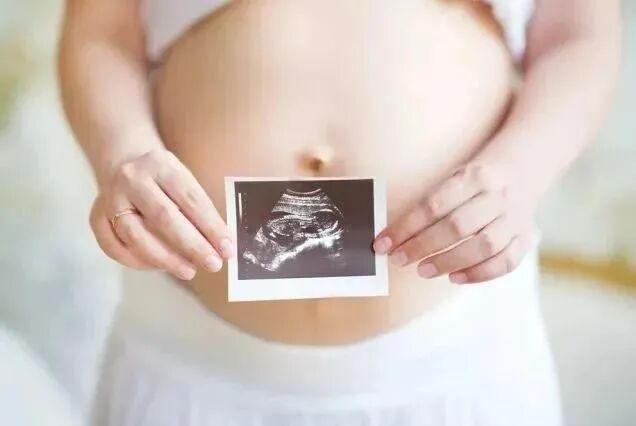

孕期让准爸妈期待的

孩子的长相占56%

整个孕期中,B超都是一项很重要的检查

不仅因为它能监测宝宝的发育和健康状况

更因为这项检查颇具神秘色彩

能透过你的肚皮

看到宝宝的模样和动作